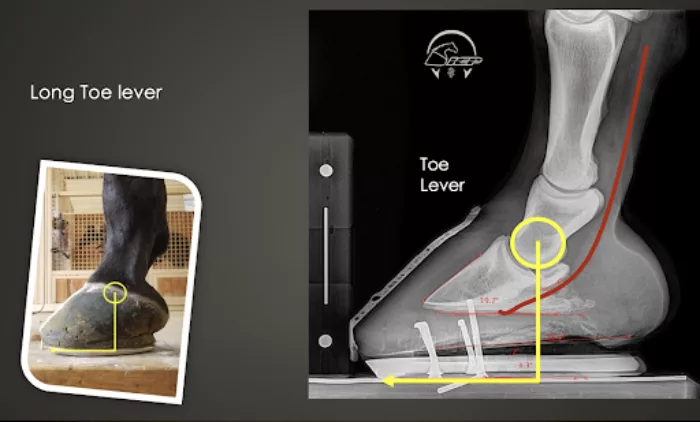

The Long Toe Lever

The first problem that is commonly seen in Western pleasure horses is a long toe lever. When describing a toe lever, Pittman looks at the center of rotation of the coffin joint. This is important because the deep digital flexor tendon sits underneath the joint. When the toe lever is long, it works against the tendon. The longer that it is, the more advantage that the ground has on pushing up on the coffin bone, pulling on the tendon and slapping the navicular bone.

Having a long toe lever can lead to a low palmar angle because long toes tend to load their heels more. On the flip side, a low palmar angle can also cause a long toe. A low palmar angle causes more tendon strain and problems in the back of the foot. This means that the coffin joint will have a low angle. A low coffin joint angle will cause horses to have a long toe and low heel. Without the help of X-rays, it can be difficult for farriers to map out the bone angle and design a management program for the horse.

Without the help of X-rays, it can be difficult for farriers to map out the bone angle

and design a management program for the horse. This horse has a coffin bone with

a 39.7-degree angle. This angle, along with the long toe lever, can be a major piece

of the puzzle to lameness cases.

In the example shown above, the horse has a coffin bone with only a 39.7-degree angle. This angle, along with the long toe lever, can be a major piece of the puzzle to lameness cases. The farrier had a 3-degree wedge pad on the horse at the time; however, the horse still has a negative palmar angle and a poor digital alignment. A horse with this naturally low coffin bone angle should never be in a perfect perimeter fit, traditional, normal, or full-toed type shoe, in Pittman’s opinion. If you compare most average healthy feet that have no leverage problems, the center of this coffin joint will be in the middle of the foot; the coffin bone angle will be about 50 degrees. Being in the low 40s or 30s means that the horse will require some type of specialty measures to correct the low angle and maintain soundness.